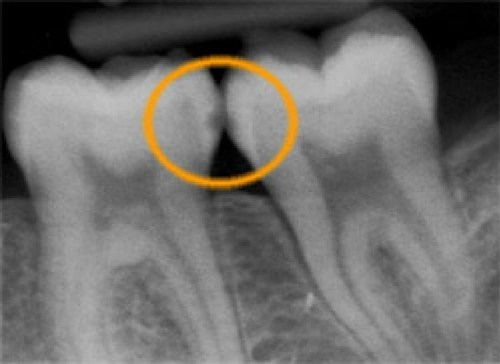

Huller mellem tænderne

Ofte dannes hullerne også mellem tænderne, hvor man ikke kan se dem med det blotte øje. Det kan derfor være nødvendigt, at tage røntgenbilleder af tænderne, for at opdage hullerne.

Første røntgenbillede viser et begyndende hul.